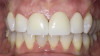

Fig 10. Final maximum intercuspation immediately after delivery of restorations.

Figure 10

The final outcome of the case met the patient's primary concerns, achieving the lengthening and lightening of the anterior teeth that she desired (Figure 10). As a clinician, the author noted several areas in the patient's overall smile where a more ideal result could have been achieved. However, because of the patient's continued challenges with GERD, she reported having difficulty with compliance related to clear aligner therapy and whitening protocols. Nonetheless, the patient was pleased with her new smile and the clinician was satisfied with the clinical results of the final restorations.